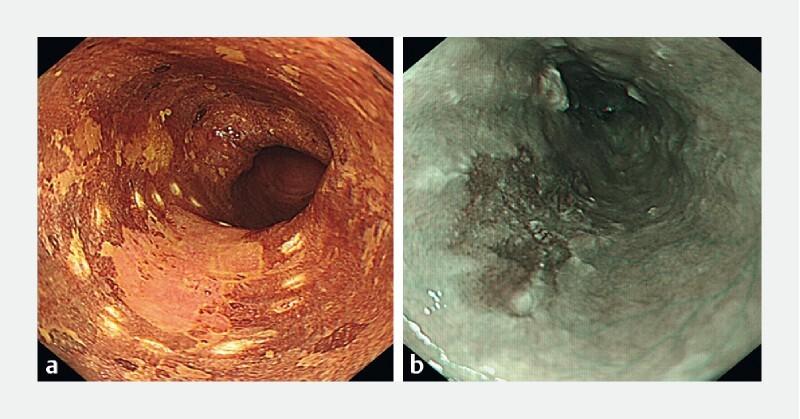

Recent evidence suggests that lugol chromoendoscopy (LCE) and narrow-band imaging (NBI) have comparable sensitivity for detection of superficial esophageal squamous cell carcinoma (SCC). However, LCE is time-consuming and associated with side effects. The aim of this study was to compare the effectiveness of NBI and LCE in defining resection margins of esophageal SCC. This was a retrospective observational cohort study of patients with esophageal SCC and dysplasia who underwent en-bloc resection between 1999 and 2017 at the Cliniques universitaires Saint-Luc, Brussels. Two groups were defined: 1) inspection with NBI only; and 2) inspection with LCE (with or without NBI). The primary endpoint was complete lateral resection rate. Multivariate regression was used to adjust for potential confounders. A total of 102 patients with 132 lesions were included. Lesions were inspected with LCE in 52 % (n = 68) and with NBI only in 48 % (n = 64). Lesions 0-IIa were more frequent in the NBI group (37 %) and 0-IIb (60 %) in LCE. Lesion location, size, and histology and resection technique (endoscopic submucosal dissection in 122/132 cases, 92 %) were similar between the groups. The rate of complete lateral resection for invasive carcinoma was 90 % in LCE group and 94 % in NBI group (  = 0.498) and 65 % and 67 % (  = 0.813), respectively, for dysplasia complete lateral resection. These results remained non-significant after adjusting for potential confounders. Mucosal inspection and delineation of tumors with lugol chromoendoscopy before endoscopic resection of esophageal squamous cell lesions was not associated with increased complete lateral resection rate when compared to NBI.

近期证据表明,卢戈氏染色内镜检查(LCE)和窄带成像(NBI)在检测浅表性食管鳞状细胞癌(SCC)方面具有相当的敏感性。然而,LCE耗时且伴有副作用。本研究的目的是比较NBI和LCE在确定食管SCC切除边缘方面的有效性。这是一项对1999年至2017年在布鲁塞尔圣吕克大学医院接受整块切除的食管SCC和发育异常患者的回顾性观察队列研究。定义了两组:1)仅用NBI检查;2)用LCE检查(有或无NBI)。主要终点是完全侧方切除率。采用多变量回归来调整潜在的混杂因素。共纳入102例患者的132个病变。52%(n = 68)的病变采用LCE检查,48%(n = 64)的病变仅采用NBI检查。NBI组中0-IIa期病变更常见(37%),LCE组中0-IIb期病变更常见(60%)。两组之间病变位置、大小、组织学和切除技术(132例中有122例采用内镜黏膜下剥离术,92%)相似。浸润性癌的完全侧方切除率在LCE组为90%,在NBI组为94%(P = 0.498),发育异常的完全侧方切除率分别为65%和67%(P = 0.813)。在调整潜在混杂因素后,这些结果仍无统计学意义。与NBI相比,但在内镜切除食管鳞状细胞病变之前,用卢戈氏染色内镜进行黏膜检查和肿瘤勾画与完全侧方切除率增加无关。